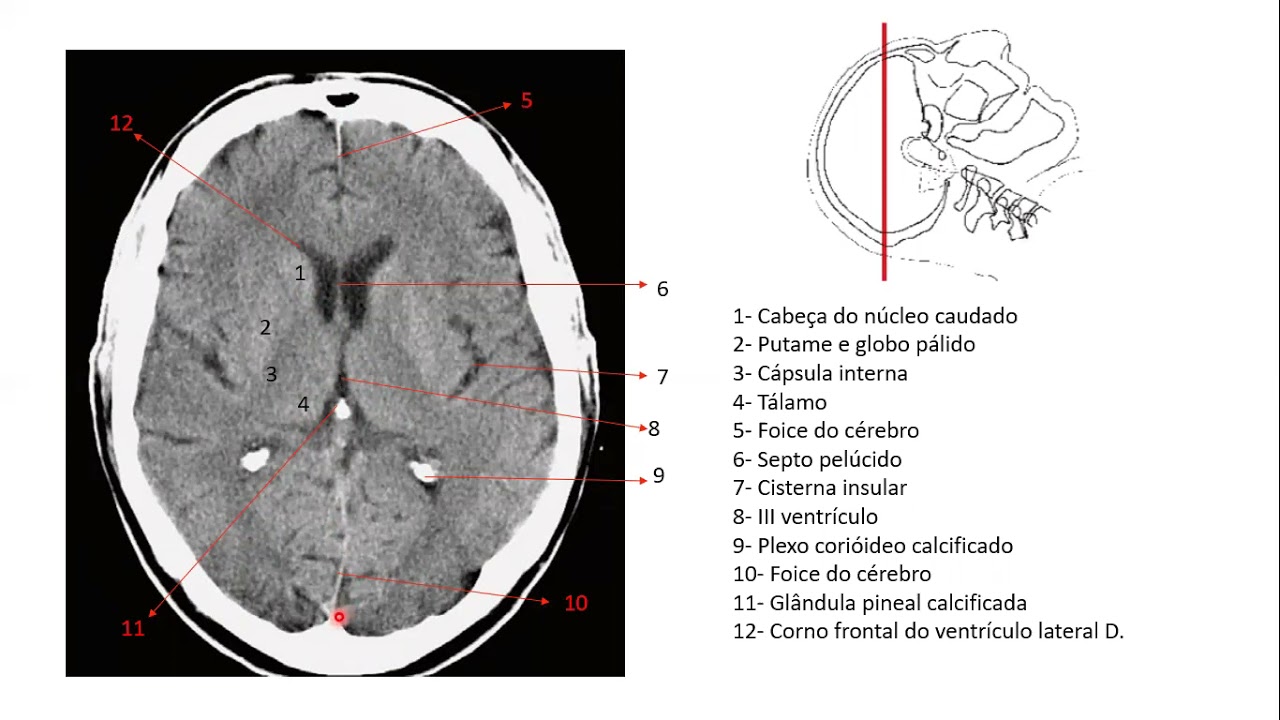

que o corpo caloso tem o joelho o corpo e o esplênio do corpo caloso nessa imagem em corte axial você consegue visualizar o joelho e o que seria o esplênio do corpo caloso Bom agora eu vou pegar uma imagem que dá pra gente visualizar bem os núcleos da base aqui pintado de verde a gente consegue visualizar o que seria o núcleo lente fore que é em formato de lente pode perceber que ele forma uma espécie de uma lente e ele é formado pela junção do putam e do Globo pálido lateral e o globo pálido Medial

aqui é bom dar um zoom deixar em tela cheia para visualizar mas dá pra gente ver a cápsula externa o que seria a cápsula externa né para visualizar melhor coloquei essa imagem que a gente tem do do do morfo funcional que dá para ver aqui ó o número sete seria a cápsula extrema o nove o claustrum e o oito a cápsula externa né então ali naquela naquela imagem anterior tá na verdade estão esses três juntos né aqui pintado de vermelho tô representando aqui pintado de vermelho eu tô representando a cápsula interna a cápsula interna também

é dividida em porções né de porção anterior o corpo e a porção posterior depois também vou fazer um vídeo colocando as principais funções dessas áreas que a gente tá falando aqui pintado de Laranja dá pra gente visualizar o núcleo calado que acompanha o ventrículo lateral em roxo a gente consegue visualizar o tálamo e agora um corte sagital pra gente visualizar algumas estruturas algumas repetidas e outras novas aqui como já tinha falado joelho corpo e esio do corpo caloso em verde o ventrículo lateral aqui em rosa representando O Aqueduto mesencefálico ou Aqueduto de silvios que vai